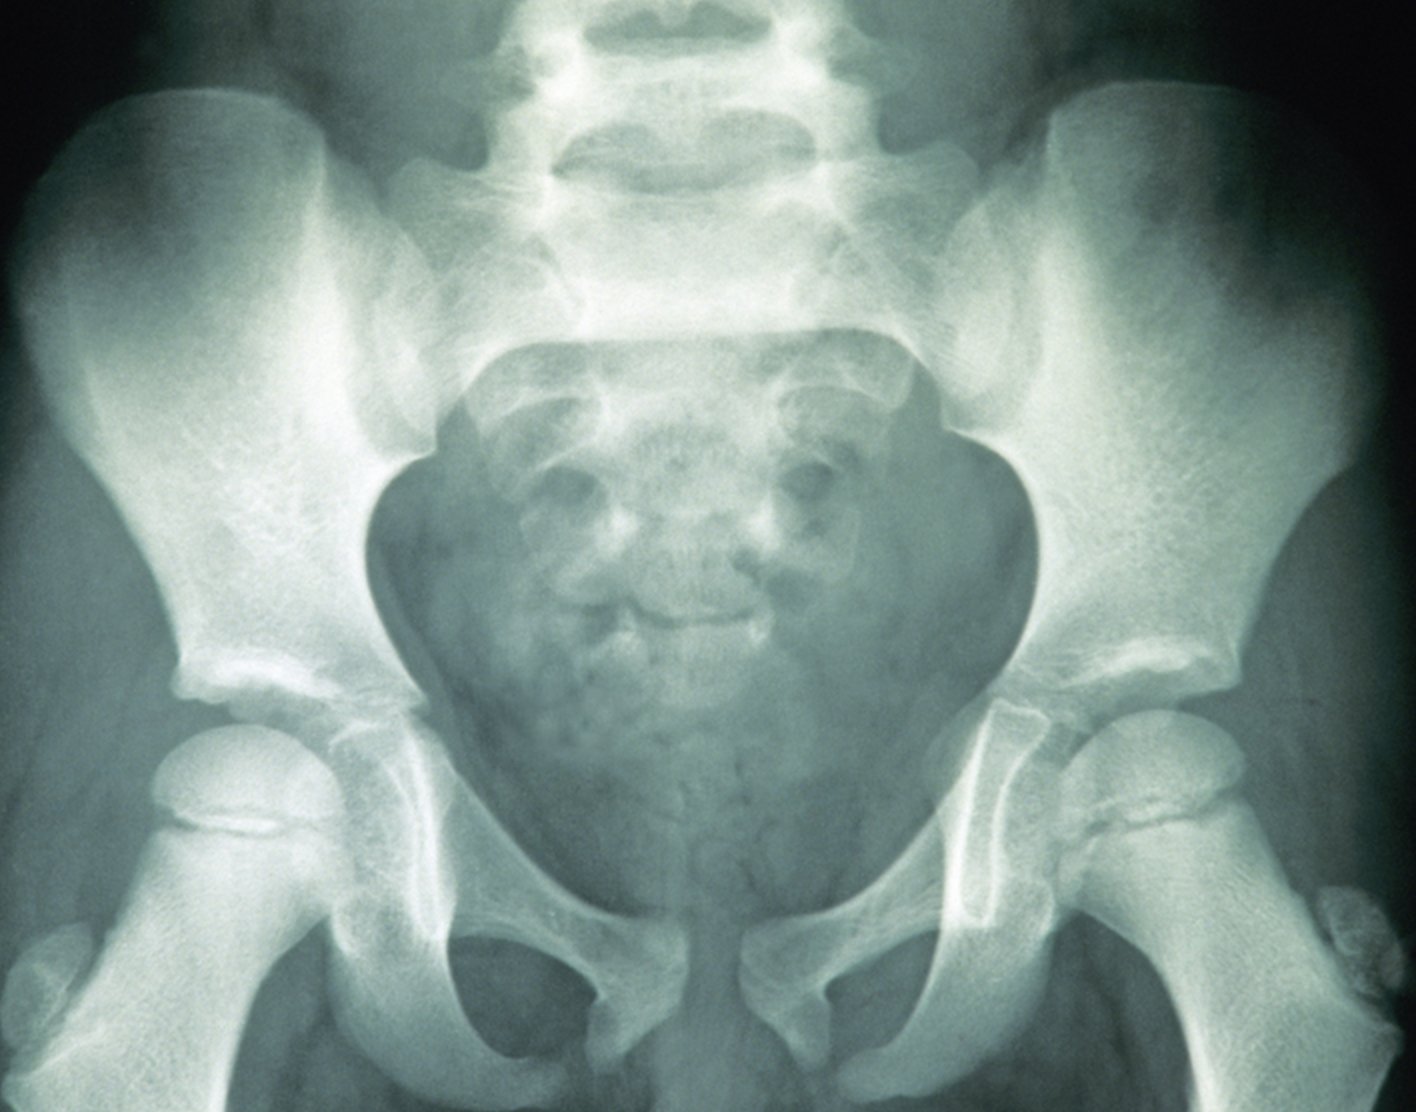

Pelvis x-ray

Definition

A pelvis

The x-ray is used to look for:

Fractures - Tumors

- Degenerative conditions of bones in the hips, pelvis, and upper legs

- Abnormal shape of your bones or joint

What Abnormal Results Mean

Abnormal results may suggest:

- Pelvic fractures

- Arthritis of the hip joint

- Tumors of the bones of the pelvis

- Sacroiliitis (inflammation of the area where the sacrum joins the ilium bone)

Ankylosing spondylitis (abnormal stiffness of the spine and joint)- Arthritis of the lower spine

- Abnormality of the shape of your pelvis or hip joint